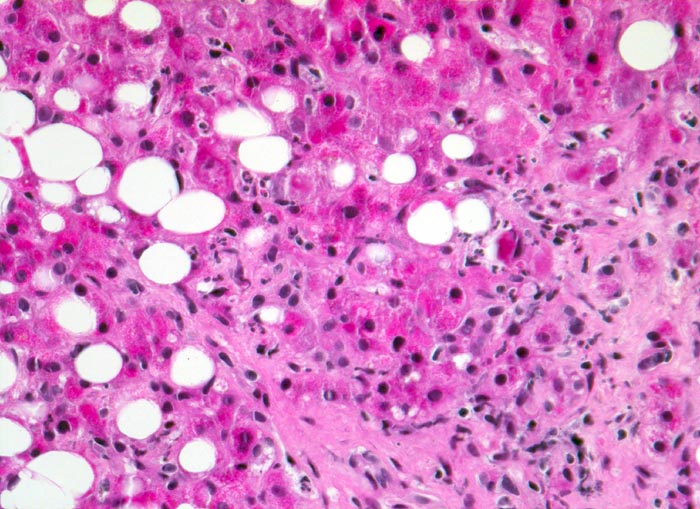

Floride alkoholische Steatohepatitis

Pathologischer Befund